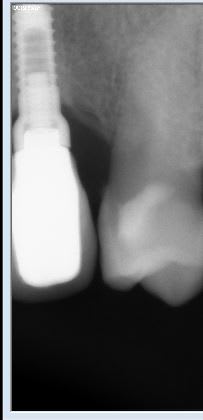

Marque d'implant?

Je voudrais savoir si quelqu'un connaît ce système implantaire.

ONB IDI

http://osseosource.com/dental-implants/product_info.php?manufacturers_id=118&products_id=853

ou ITP gold IDI

http://osseosource.com/dental-implants/product_info.php?manufacturers_id=118&products_id=856

mais c'est la même connexion...;-)